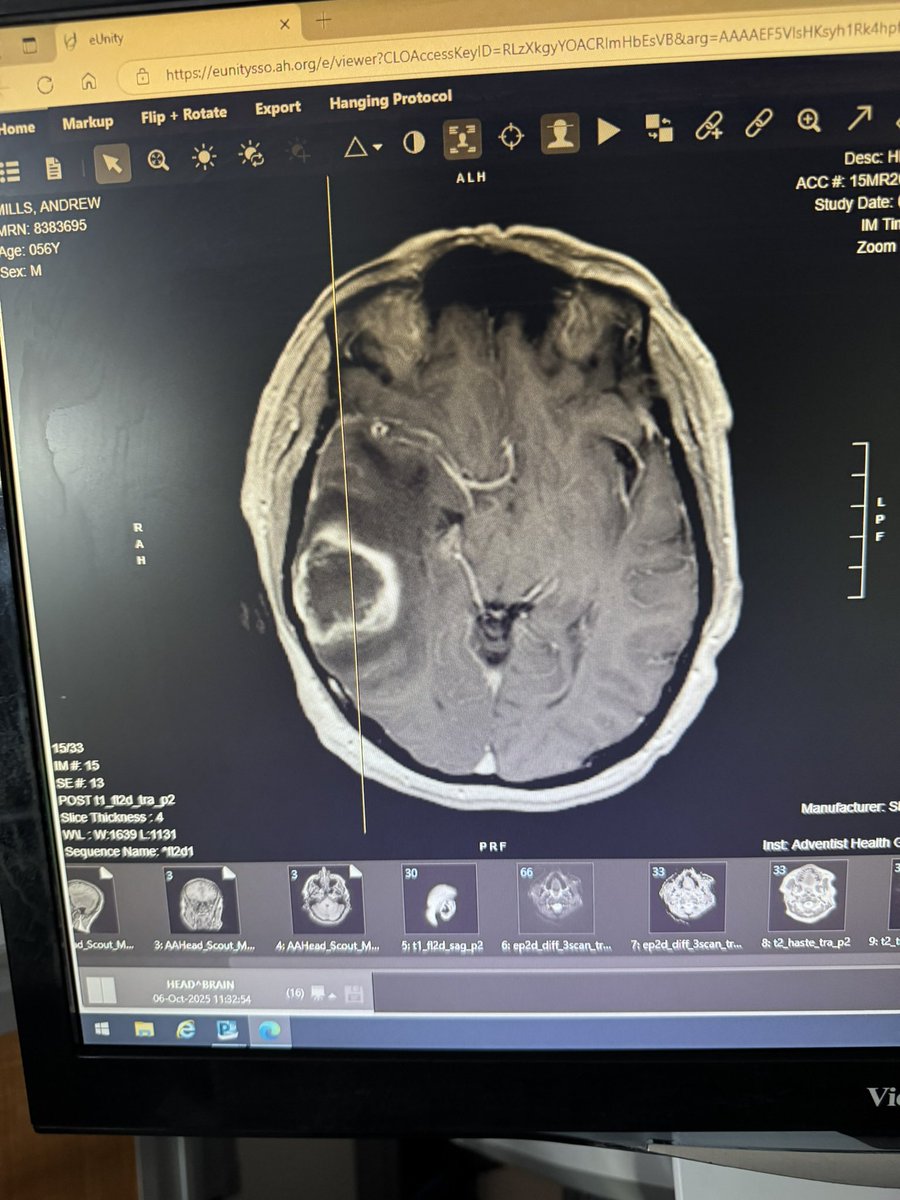

This makes me so sad, and so frustrated. @SecKennedy This girl deserves a chance. President Trump signed right to try and the @DrPatrick cannot take 15k applicants. Please give cancer patients hope. Braelyn is 16 years old. Please approve her for #ANKTIVA @bullishbruk

Today we learned that Braelyn was denied access to the Anktiva clinical trial. Trial criteria are rigid. Cancer is not. We will now pursue single patient expanded access. We are not stopping. #GBM #Anktiva #ImmunityBio #ChildhoodCancer #SaveBraelyn